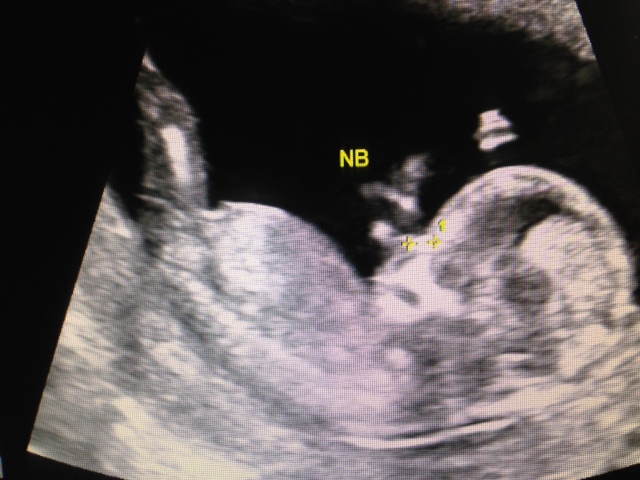

These are my pics from my scan at 12+3. I'm not really sure if you can see anything but I would love to hear your opinions.

Attachment 11722Attachment 11723Attachment 11724

Sorry I can't make out a clear enough nub to make a guess...but congrats on baby :)

I'll go boy:) Is that the tiniest bit of blue nub in pic 1??!!